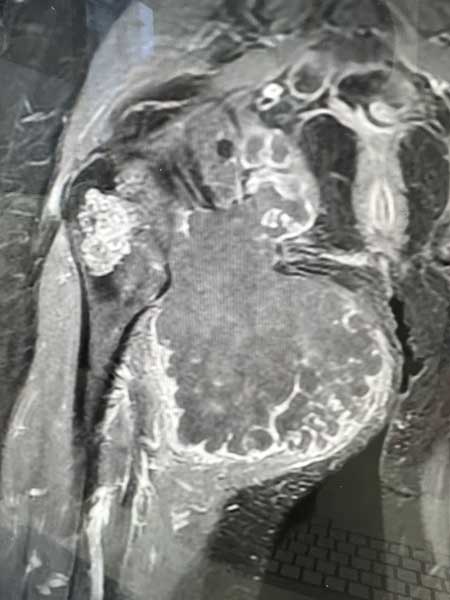

Dès 2006, il a démontré la possibilité de réaliser simultanément deux prothèses de hanche sur le même patient (références 23 à 28), stratégie qui est désormais utilisée par le Docteur Jean-Luc Raynier, et il a mis en évidence les limites des cupules de resurfaçage de hanche (référence 29). Il est également spécialiste de la reconstruction osseuse par Ingénierie tissulaire, sujet de sa thèse de science, objet de nombreuses publications internationales depuis 2005 (références 30 à 36). Enfin, le Professeur Trojani est spécialisé dans les interventions exceptionnelles en chirurgie tumorale, au niveau du genou et du bassin (Figures 3 à 5).

Figure 3 : chirurgie de résection complète du fémur avec mise en place d’une prothèse de fémur total, c’est-à-dire simultanément d’une prothèse de hanche et d’une prothèse de genou, du fait d’une tumeur osseuse atteignant tout le fémur (Sarcome d’Ewing).